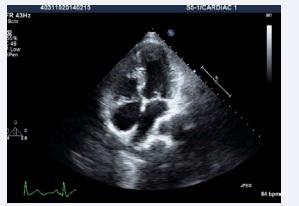

A 22-year-old male was referred to our tertiary care institute with a diagnosis of double outlet right ventricle with a ventricular septal defect and malposed great arteries. The patient was evaluated in the referring institute for atypical chest pain for ten days without any significant past history. A clinical examination, including cardiac testing, was normal, and the resting oxygen saturation was 98% on room air. Although the transthoracic echocardiographic window was poor, it revealed the patient had situs solitus, and there was AV and VA concordance. The aorta was located to the left and anterior to the pulmonary artery (Figures 1,2, video 1,2)

Figure 1: Transthoracic echocardiogram apical 4 chamber view showing AV and VA concordance